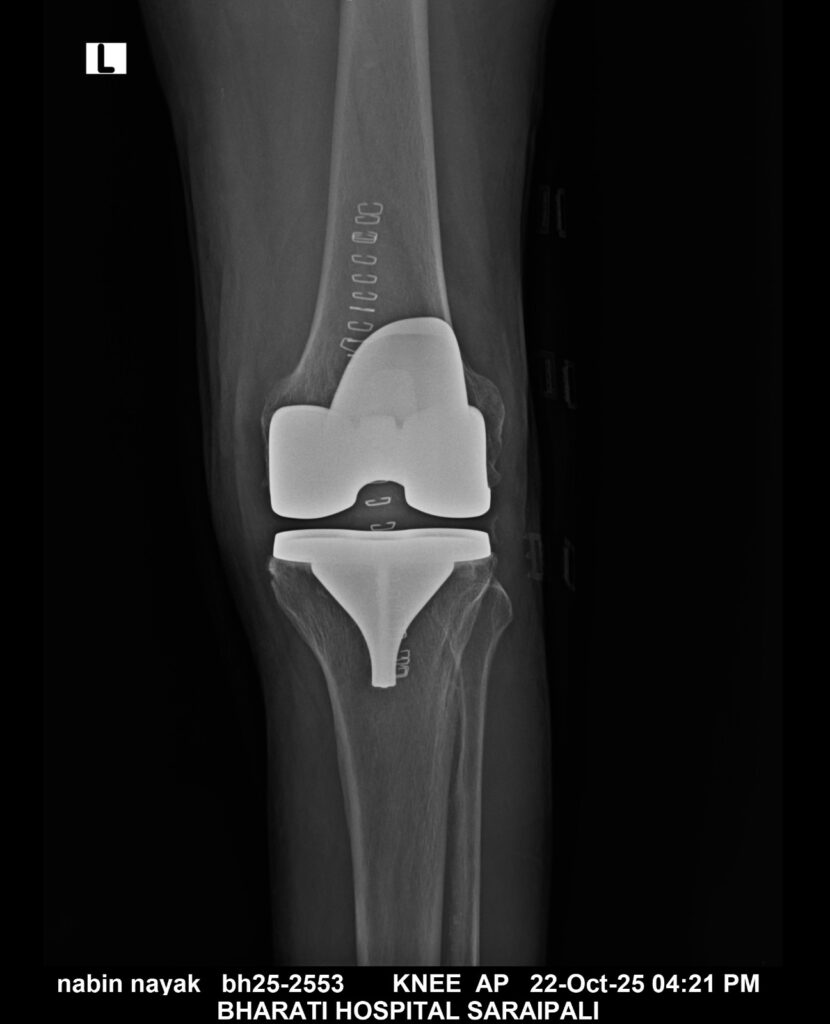

सरायपाली। भारती हॉस्पिटल सरायपाली में अब घुटने के समस्या के लिए रायपुर, विशाखापट्टनम जैसे बड़े शहरों की और जाने की कोई आवश्यकता नहीं। विगत कुछ वर्षों से एक 70 वर्षीय वृद्ध व्यक्ति बहुत दिनों से घुटने के दर्द से परेशान था और चलने फिरने में भी उनको बहुत तकलीफ होती थी।

किन्तु जब उन्होंने ईलाज के लिए भारती हॉस्पिटल में आए। इसके पश्चात् यहां पर उनका ईलाज संभव हो पाया। इस प्रत्यारोपण को डॉ सौरभ खरे और डॉ त्रिपाठी के द्वारा सफलतापूर्वक किया गया।